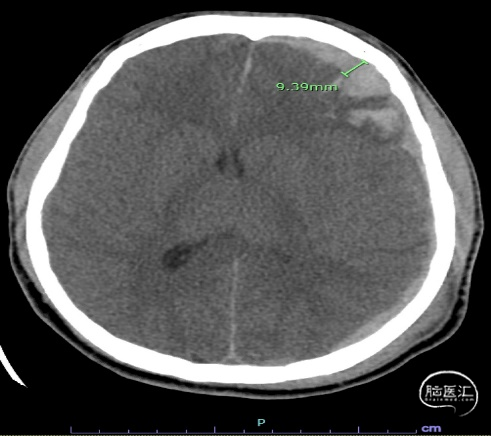

1例18岁男性患者,因癫痫发作入院,GCS评分7T。入院后给予左乙拉西坦防治癫痫发作。头颅CT、MRI检查提示,左额叶和左颞叶硬膜下出血(SDH)和脑实质出血,在顶骨和颞骨交界处线性骨折,提示钝性创伤造成颅内出血(图1)。